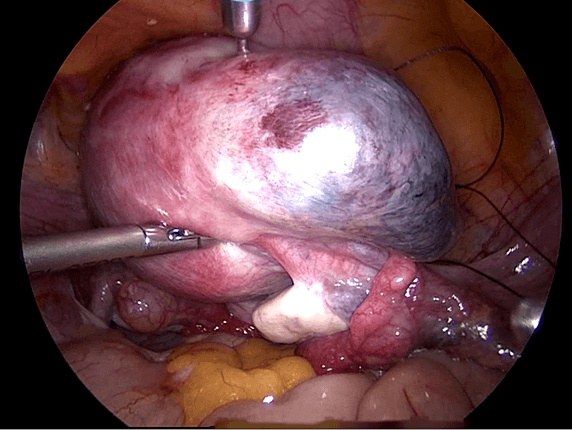

Reseksi laparoskopi kornu kehamilan ektopik

Pada tahun 2009 nyonya UDS datang mengunjungi saya , dia telah menikah 3 tahun dan dia tidak bisa hamil. Histerosalpingogram yang dilakukan di rumah sakit yang lain menunjukkan kedua tubanya tersumbat / terblokir. Dia menjalani laparoskopi , dan laparoskopi menunjukkan ukuran rahim yang normal. Kedua tuba nya normal dan dipatenkan setelah insulfasi tuba dilakukan dibawah tekanan. Dia hamil secara spontan 2 bulan setelah menjalani laparoskopi namun sayangnya kehamilan berakhir dengan aborsi yang terlewatkan. Dia telah menjalani evakuasi hasil konseptus. Pasca operasi , keadaan dia baik-baik saja akan tetapi tidak dapat hamil. Dia telah diberikan beberapa siklus klomifen sitrat namun tanpa membuahkan hasil. Pada tahun 2011, dia menjalani siklus inseminasi intrauterin setelah diberikan suntikan hormon perangsang folikel ( FSH ). Setelah prosedur dilakukan , dia hamil akan tetapi sayangnya kehamilan itu adalah kehamilan ektopik. Dia menjalani reseksi laparoskopi kornu kanan kehamilan ektopik di tahun 2011 ( Gambar 26.7 – 26.11 ) ( simak video 26.3 ). Pasca operasi di tahun 2013 dia menjalani histerosalpingografi dan menunjukkan bahwa tuba kiri tidak paten. Dia dapat hamil setelah menjalani IVF.

Pembahasan

Kornu kehamilan ektopik tidaklah umum. Biasanya didiagnosisnya terlambat karena pasien dengan kondisi seperti ini tidak memliki banyak gejala-gejala. Pecahnya kehamilan ektopik pada kornu dapat menyebabkan pendarahan yang berlebihan. Pada pasien ini diagnosis dilakukan lebih awal karena dia menjalani IUI dan berada dalam pengawasan secara teratur. Eksisi telah dilakukan dengan berhasil secara laparoskopi.